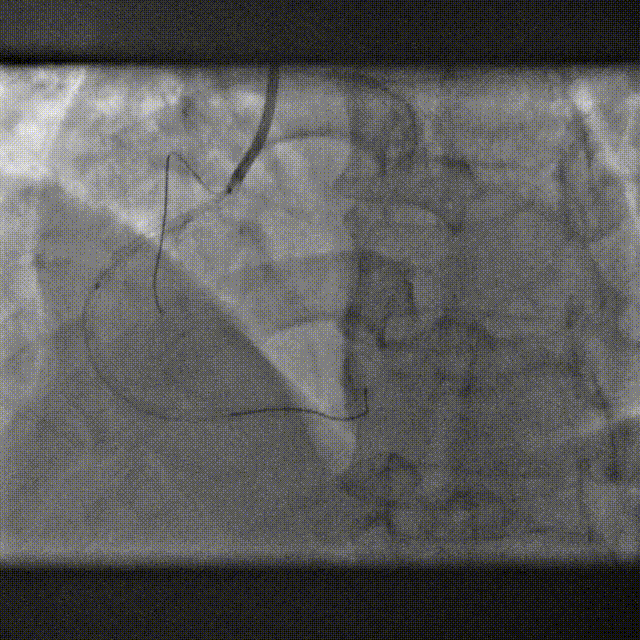

1.对于指引导管要求支撑力和操控性兼具时,可考虑使用SAL,SAL可在窦底自如旋转,出入冠容易,避免对主动脉壁的刮伤。

2.在选择SAL型号时,需考虑支撑力、操控性、头臂干的解剖形态、冠脉开口的位置进行综合考虑,选择合适的导管,事半功倍。

SAL导管特点

SAL比同型号的AL头端短 6-8 mm

头端安全,操控灵活

稳定的被动支撑,不需要过多主动操作